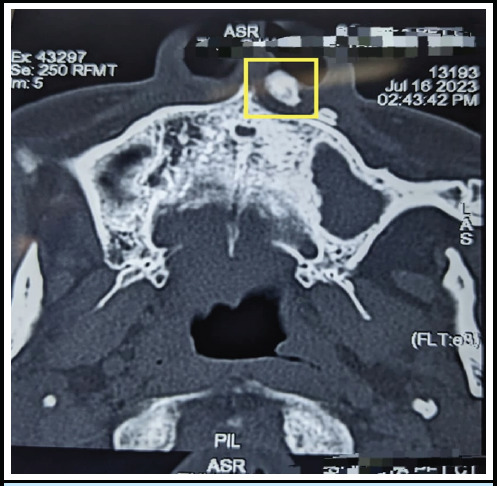

Injuries sustained from foreign bodies and burns after oil drum explosions are addressed immediately. This case reports a rare long-standing retained tooth after such an explosion. A 65-year-old male with a history of a victim of explosion injury to the face dating 20 years back with complaints of repeated nasal vestibulitis was evaluated. An X-ray of paranasal sinus followed by computed tomography of the nose and paranasal sinuses revealed a radio-opaque foreign body in the region of upper alveolus near left nasal vestibule. After consultation and clearance from dental department, exploration through the vestibule was done and the foreign body was removed without complications. Our intervention involved surgical removal of foreign body under local anesthesia. The patient has recovered following the intervention and has resumed his normal activities.